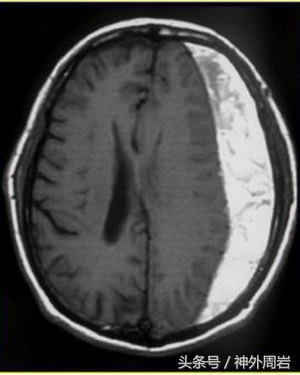

今天门诊一个64岁老人,因为头痛1个月拍了个脑CT片子,面对着脑出血的诊断,一脸茫然,不知所措。反复地陈述“怎么可能?!”难道是不知不觉中发生的?

对,这种脑出血就是在不知不觉中发生的——慢性硬膜下血肿,而且受害群众绝大多数都是老年人。

慢性硬膜下血肿是临床常见病之一,因其发病隐匿,很容易被其他疾病掩盖临床症状,所以这是很容易被贻误的疾病。一旦罹患此病,给人的感觉就是“不知不觉”。